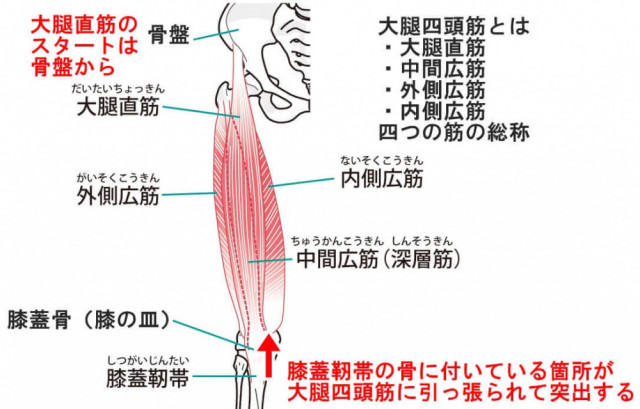

下の大腿四頭筋の図をご覧下さい。

大腿四頭筋は下の四つの筋肉から出来ています。

「大腿直筋」「内側広筋」「中間広筋」「外側広筋」

このうち、大腿直筋は骨盤から始まっています。

つまり、骨盤の歪みも影響してくる事になります。

そのため施術では骨盤の調整も必要と考えています。